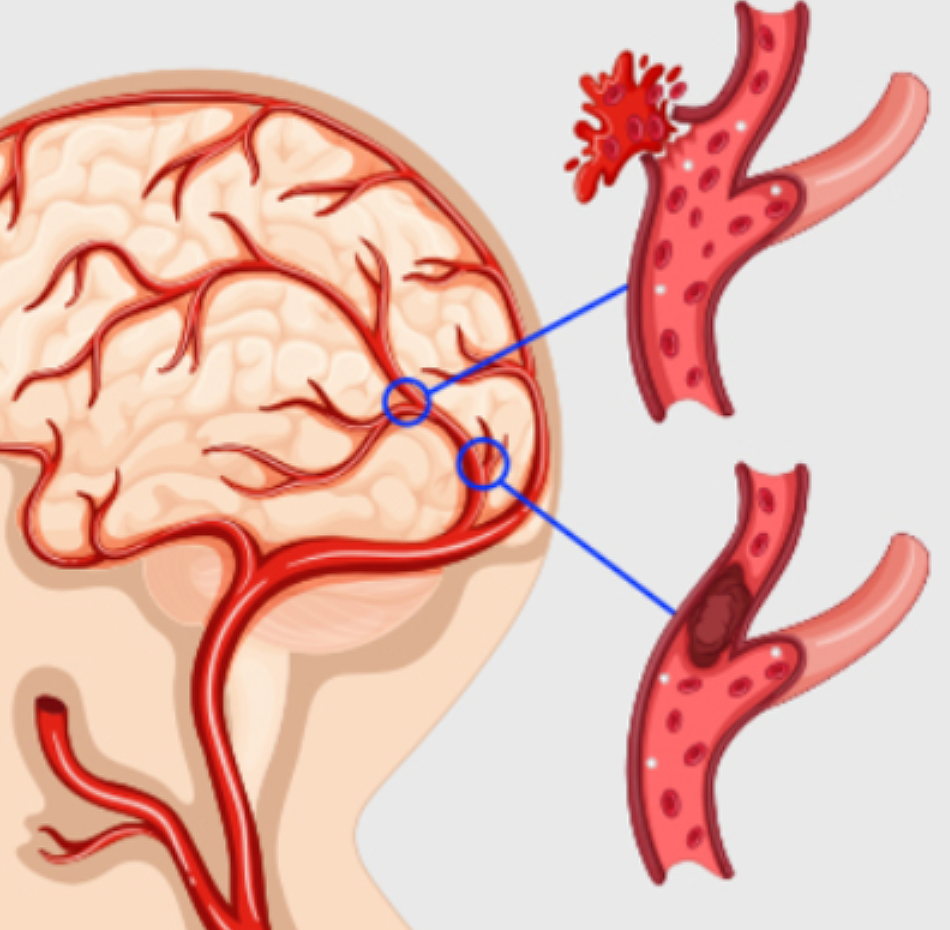

갑자기 뇌혈관이 막히면 뇌의 일부가 손상되고 정상적인 활동이 불가능하게 되며 장애가 나타나게 됩니다. 이를 뇌경색이라고 합니다. 목 부분에 있는 경동맥, 척추, 기저동맥부터 뇌 안에 있는 동맥까지 어느 혈관이든 막힐 수 있는데, 이로 인해 해당부위의 뇌가 괴사하면서 지속적으로 증상이 발생할 수 있습니다

간혹 뇌졸중이나 뇌출혈과 혼동하는 경우가 있는데, 혈관이 막혀서 뇌에 피가 공급되지 않으면 뇌경색이고, 뇌속의 혈관이 터지면 뇌출혈이라고 합니다. 그리고 이 두 질병을 합쳐서 뇌졸중이라고 부릅니다. 과거에는 뇌출혈 환자가 많았지만 최근에는 전체 환자의 60~70%가 뇌경색 환자입니다. 건강보험심사평가원 자료에 따르면 2018년 뇌출혈로 병원을 방문한 환자는 99,811명이고 뇌경색 환자는 503,241명으로 뇌경색 환자가 5배 이상 많습니다.

뇌경색은 원인에 따라 뇌혈전증과 뇌색전증으로 구분할 수 있습니다. 뇌혈전증은 뇌혈관 자체에 혈전이 나타나서 혈관이 점차 좁아지다가 막히는 질병입니다. 반면 뇌색적은 심장 등 다른 부위에서 나타난 혈전이 혈관을 타고 올라와서 뇌동맥을 막는 것을 말합니다. 뇌경색은 죽어가는 뇌세포를 살리기 위해 1분 1초가 중요한 응급질환입니다. 증상이 발생한 후 3시간 이내로 치료를 해야되서 초기 증상이 나타났다면 즉시 병원에 방문해야 합니다.